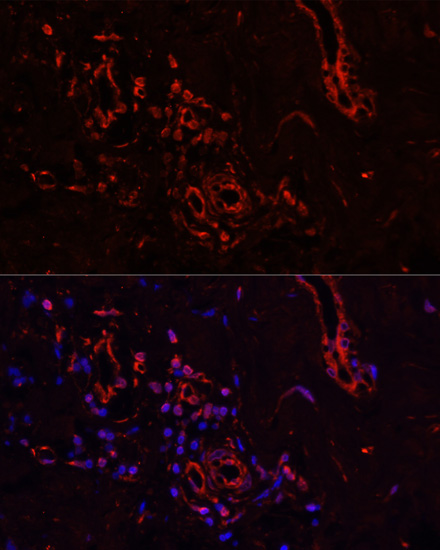

Immunofluorescence analysis of rat ovary using COL1A1 antibody.

Immunofluorescence analysis of human breast cancer using COL1A1 antibody.